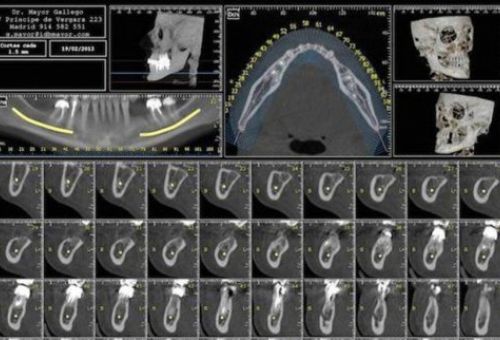

Se trata de un escáner intraoral que obtiene imágenes en tres dimensiones de la mandíbula y cada una de las piezas dentales y huesos.

Las imágenes que se obtienen, mediante cortes y rayos X, nos permiten hacernos una idea muy clara de la situación de las piezas dentarias, sus características, su estado y las características de los tejidos blandos que las rodean.

Permite conocer con precisión la estructura ósea y de tejidos blancos de toda la boca y mandíbula.

Permite ver diferentes puntos de vista de una misma pieza dentaria, fundamental para decidir qué tratamiento es el más adecuado.

La precisión de esta prueba permite observar las estructuras dentales y maxilares en tres dimensiones, lo que facilita el diagnóstico y tratamiento

- Implantología. Con esta prueba conoceremos mejor la estructura ósea del paciente y asegurar así el éxito con la colocación del implante.